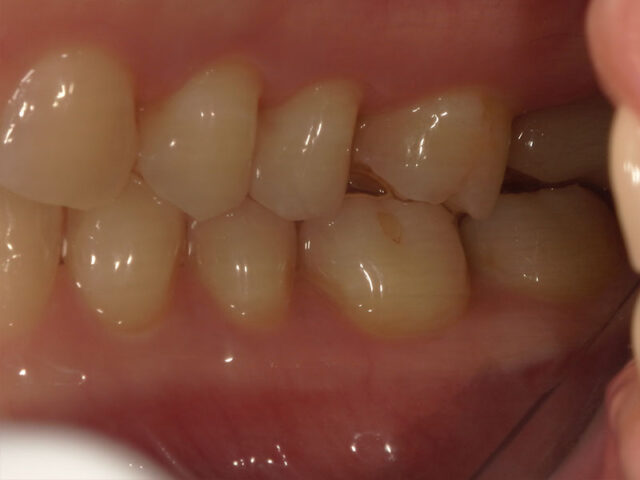

最終補綴装着

治療期間1年

補綴かみ合わせの状態

補綴物装着後